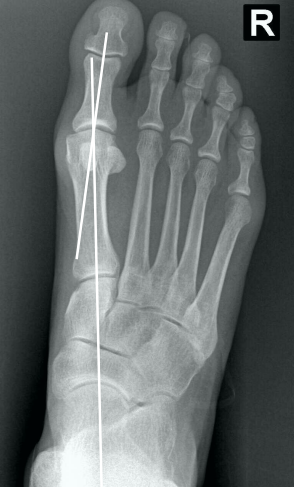

• Na avaliação radiográfica em AP com carga, quais os principais ângulos a serem traçados?

• Ângulo de valgismo do hálux (metatarsofalângico)

• Ângulo intermetatarsal

• Ângulo de valgismo interfalângico do hálux

• Ângulo articular metatarsal distal (AAMD)

• Na radiografia em AP com carga, como é traçado o ângulo intermetatarsal?

• Ângulo entre o eixo longo do 1° e do 2° raio

• Normal → até 9°

• Leve → 9° a 12°

• Moderado → 13° a 15°

• Grave → > 16°

• Na radiografia em AP com carga, como é traçado o ângulo de valgismo do hálux (metatarsofalângico)?

• Ângulo entre o eixo longo do 1° mtt e o eixo longo da falange proximal

• Normal → até 15°

• Leve → < 25°

• Moderado → 25° a 40°

• Grave → > 40°

• Na radiografia em AP com carga, como é traçado o ângulo de valgismo interfalângico do hálux?

• Ângulo entre o eixo longo da falange proximal e o eixo longo da falange distal

• Normal → até 10°

• Na radiografia em AP com carga, como é traçado o ângulo articular metatarsal distal (AAMD)?

• Traça-se uma linha unindo os dois pontos mais largos da superfície articular do 1° mtt e outra linha perpendicular a esta

• Depois, traça-se uma linha no eixo longo do 1° mtt

• O ângulo entre as duas maiores retas → até 15°

• Como verificar na radiografia AP com carga, se há luxação do sesamóide e classifica-lo de acordo com Mann e Coughlin?

• Traça-se um linha no eixo do 1° mtt e verifica o quanto, em “%”, a linha toca o sesamóide tibial (medial)